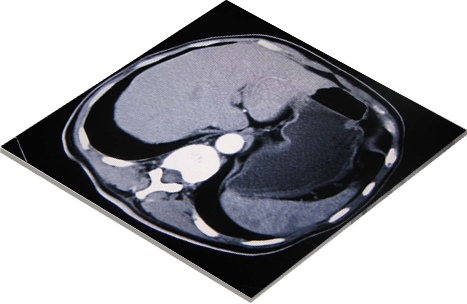

远程影像同步操作

实现在不同地点,使用不同设备同步浏览图像,一方操作,其他客户端可以同时浏览相同的影像:包括影像的查看,操作,测量等功能